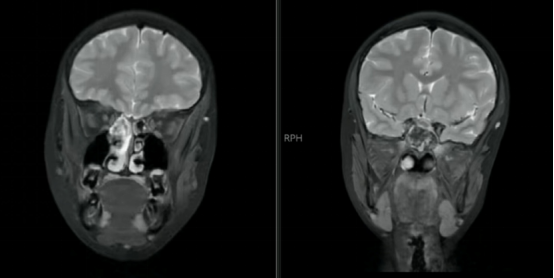

影像结果显示蝶窦已被真菌团块填满,像塞了一团“发霉的棉花”

孙亚男教授解释,蝶窦位置深,结构隐蔽,此处的真菌感染一旦形成,炎症产物会积聚、压迫三叉神经末梢,从而引发剧烈的头痛,药物治疗往往难以清除病灶,效果欠佳。对于鑫鑫这种情况,手术是解除痛苦、根除病灶最直接有效的方法。